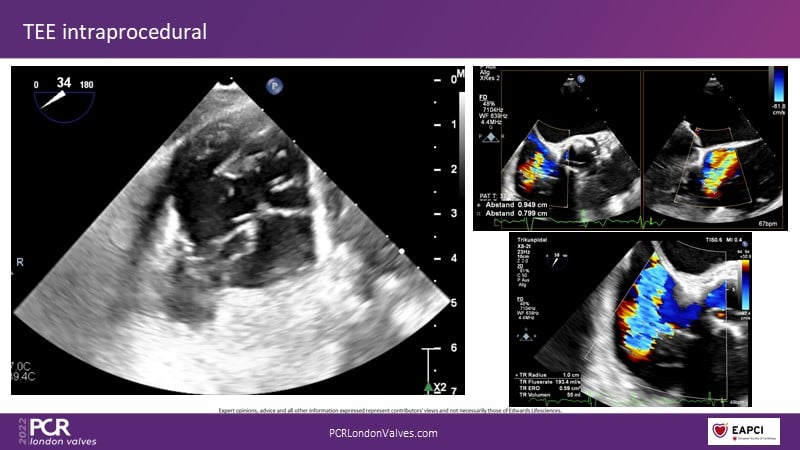

This innovative session takes you through the patient selection and anatomical characteristics when selecting amongst the different transcatheter options to treat tricuspid regurgitation, followed by a recorded demonstration using the PASCAL Precision repair system.